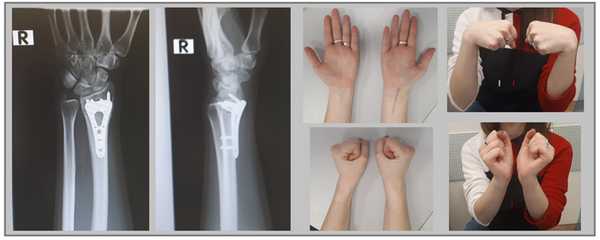

Клинический пример лечения перелома дистального метафиза лучевой кости при помощи открытой репозиции и остеосинтеза пластиной.

Пример 1.

Пациентка М 65 лет, травма в результате падения на улице с опорой на кисть. В анамнезе множественные переломы, миеломная болезнь в стадии ремиссии (7 лет). После падения обратилась в РТП где ей была наложена гипсовая повязка. По какой то причине репозиция не производилась. После обращения в нашу клинику госпитализирована для оперативного лечения.

Внешний вид конечности после снятия гипсовой повязки. Рентгенограммы выполненные при помощи ЭОП на операционном столе выявили полное смещение всего дистального метафиза лучевой кости к тылу на целый поперечник.

Но наша пациентка хотела максимального восстановления функции, силы хвата, амплитуды движений и нормальных анатомических взаимоотношений своей конечности, по этой причине было принято решение о выполнении операции.

Интраоперационно под контролем ЭОП произведена закрытая репозиция перелома.

После репозиции на рентгенограммах отчётливо виден многоооскольчатый, нестабильный характер перелома.

Произведён доступ к месту перелома по ладонной поверхности предплечья. При ревизии выявлено множество мелких осколков в метафизарной области по волярному кортексу. Произведена открытая репозиция перелома, временная фиксация спицами. Накостно уложена пластина VA-LCP™ Two-Column Distal Radius Plate

После рентгенконтроля производится введение блокируемых винтов диаметром 2,4 или 2,7 мм.

Данная пластина отлично подходит для фиксации оскольчатых переломов дистального метаэпифиза лучевой кости, однако в ряде случаев, когда перелом располагается более дистально, предпочтительнее использовать пластину другой конструкции (Volar rim).

Окончательный остеосинтез после проведения всех винтов выглядит на рентгенограмме примерно так. На левой части рисунка схематично отображено расположение фрагментов кости, фиксированных пластиной.

Функция конечности через 3 недели после остеосинтеза.

В более простых случаях, когда суставная поверхность представлена одним большим фрагментом кости, фиксация LCP пластиной настолько надежная и стабильная, что позволяет начать активную разработку движений уже на следующий день после операции, и использовать руку для бытовых нужд уже через 2 недели после операции.

Например у Пациентки А, 24 лет, операция выполнена по поводу относительно простого перелома дистального метаэпифиза лучевой кости с угловым смещением к тылу на 30 градусов и укорочением лучевой кости на 7 мм. Учитывая молодой возраст и высокие функциональные запросы принято решение о выполнении остеосинтеза. Учитывая сохранность волярного кортекса использована пластина меньшего размера, которая установлена более проксимально, с целью максимального сохранения кровоснабжения эпифиза лучевой кости.

Через 6 недель наблюдается рентгенологическое сращение перелома. Функция конечности к этому времени уже практически полностью восстановлена.